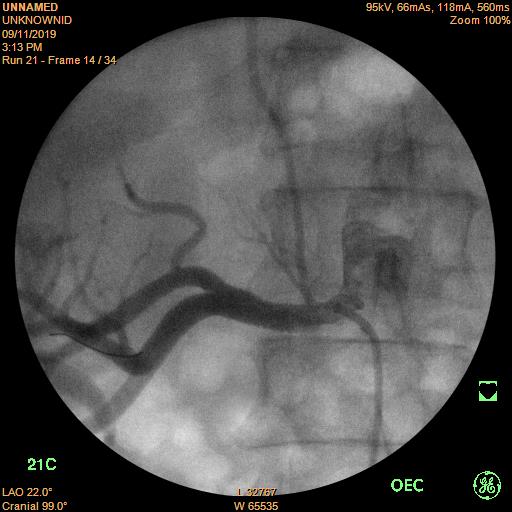

Sau khi nong bằng bóng để làm nở vị trí hẹp, một stent kích thước 7.0x19 mm được đặt vào vị trí hẹp, chụp mạch máu thấy dòng chảy tốt, vị trí hẹp động mạch thận trước đây đã trở lại kích thước bình thường.

Hình 3. Động mạch thận phải sau khi đặt stent.

Sau khi đặt stent và trị số huyết áp của bệnh nhân đã giảm xuống mức tối ưu 130/80 mmHg.